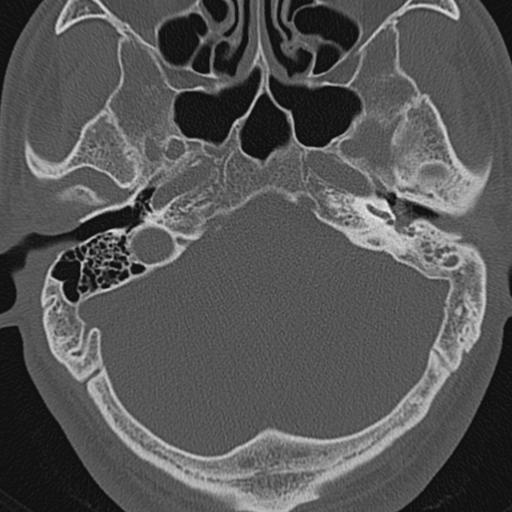

以下是引用zxl51642在2009-8-25 13:37:00的发言:[br]1、左侧慢性硬化型中耳乳突炎(中耳鼓室腔及听小骨受累),并胆脂瘤形成;2、左侧外耳道软组织密度影填塞,考虑炎性肉芽肿,建议结合临床;3、右侧颈静脉窝较左侧明显扩大,不排除颈静脉球瘤,建议mr进一步检查。

以下是引用随光逐影在2009-8-25 19:05:00的发言:[br]1)左侧慢性中耳乳突炎(肉芽肿或胆脂瘤形成),左侧外耳道炎性肉芽肿。2)右侧颈静脉球高位。